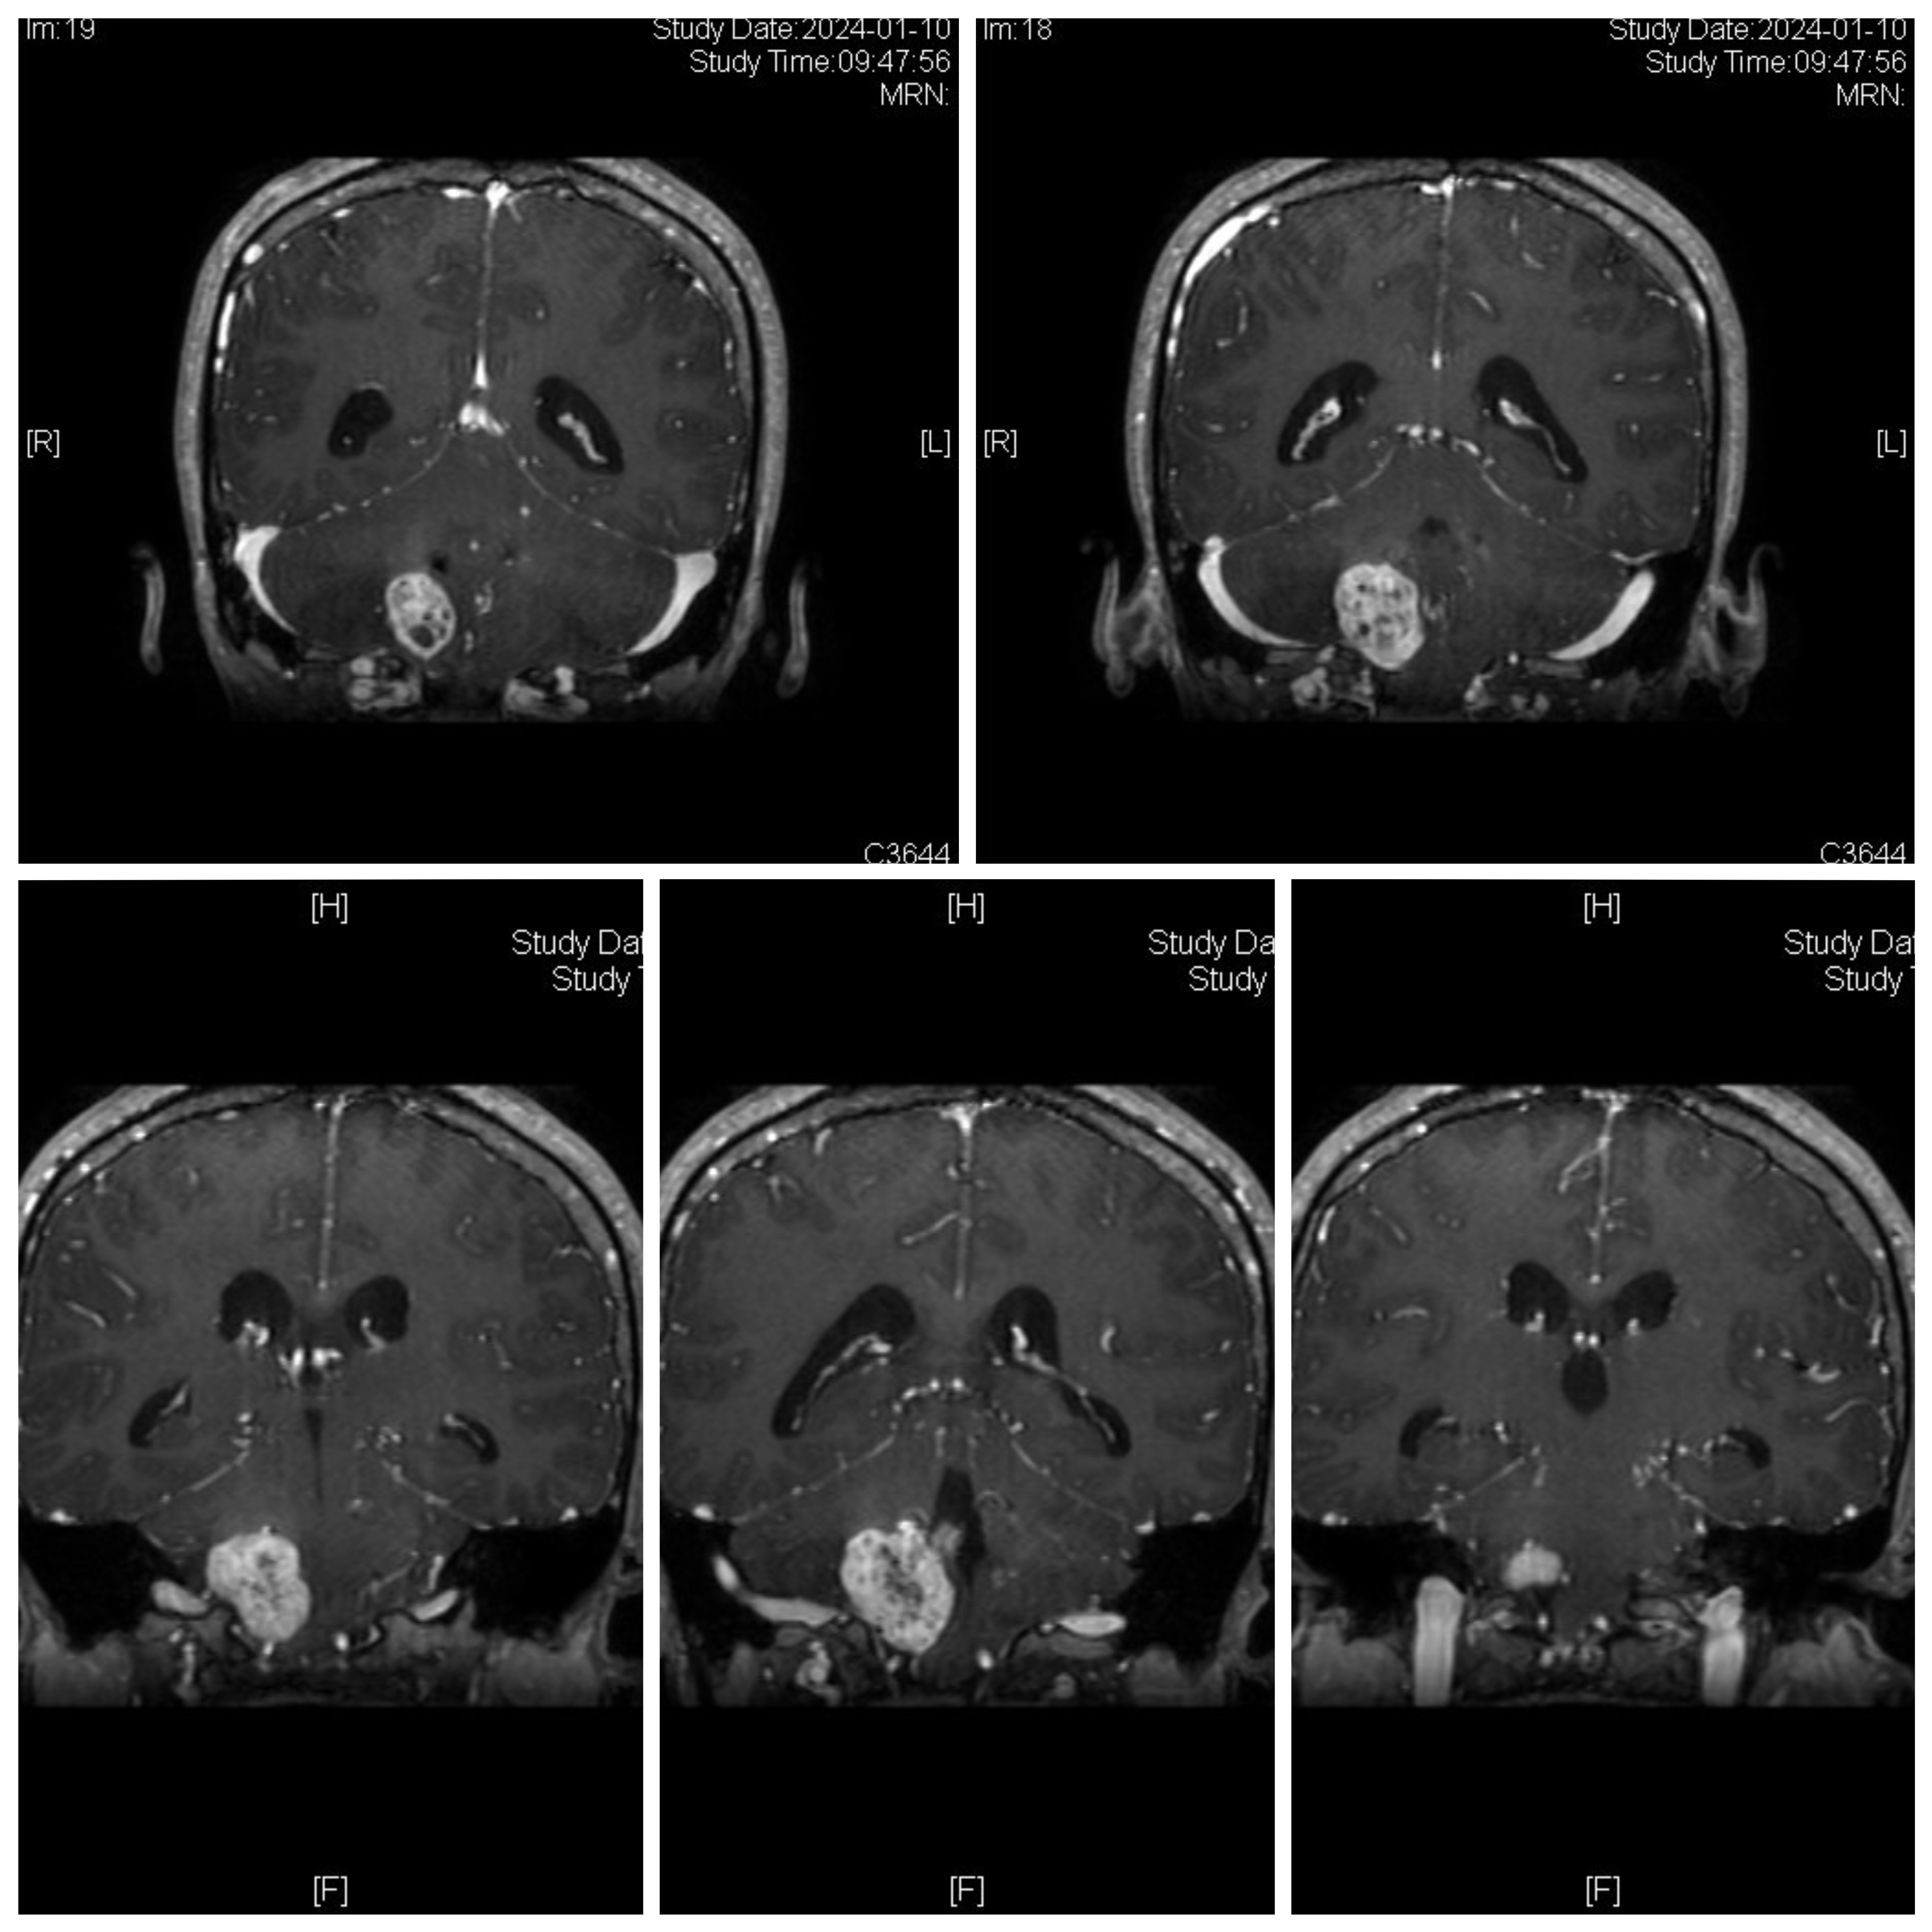

女性患者,26岁,因“间断性头晕1月余。”于2024-01-08入院。

诊断:延髓血管母细胞瘤

von Hippel-Lindau综合征